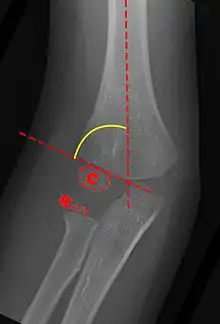

Anterior X-ray

Carrying angle can be evaluated through AP view of the elbow by looking at the Baumann's angle.[3] There are two definitions of Bowmann's angle:

The first definition of Baumann's angle is an angle between a line parallel to the longitudinal axis of the humeral shaft and a line drawn along the lateral epicondyle.

Another definition of Baumann's angle is also known as the humeral-capitellar angle. It is the angle between the line perpendicular to the long axis of the humerus and the growth plate of the lateral condyle. Reported normal values for Baumann's angle range between 9 and 26°.[7] An angle of more than 10° is regarded as acceptable.[7]